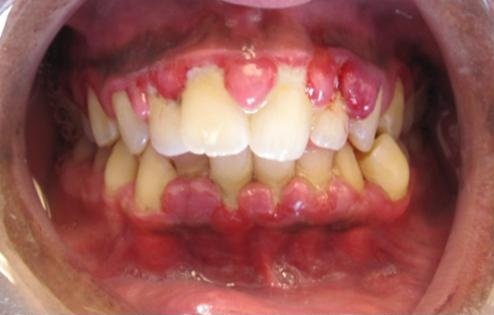

Foto: Penyakit gusi gingivitis

Bau mulut pada pasien dengan penyakit gusi disebabkan oleh gas volatil berbau tajam atau volatile sulfur compounds (VSCs) seperti hidrogen sulfida (H₂S) dan metil merkaptan (CH₃SH). Gas tersebut dihasilkan oleh mikroorganisme anaerob Gram-negatif yang hidup di saku periodontal, plak subgingival, dan permukaan lidah.